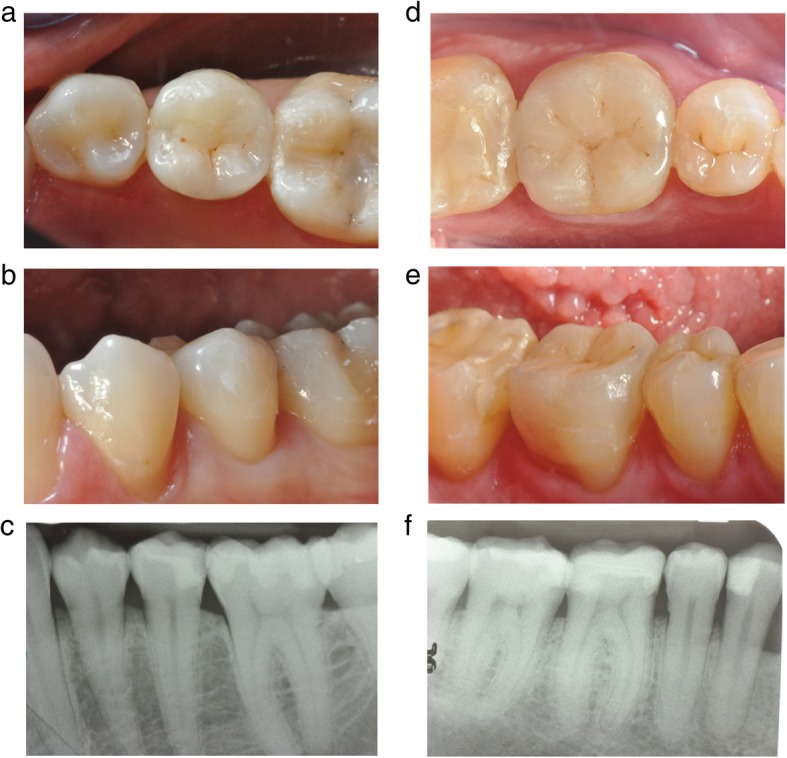

The FIT evaluation was performed only at last recall (3-year follow-up) by an experienced operator (Fig. 1 a-f).

Fig. 1.

a, b and 1c. are related to a clinical case of Group 1 (the second premolar received a IPS e.max press restoration) while Fig. 1 d, e and f of Group 2 (the first molar received a GC Initial™ LiSi Press restoration). No technical or biological complications were observed at 3-year recall